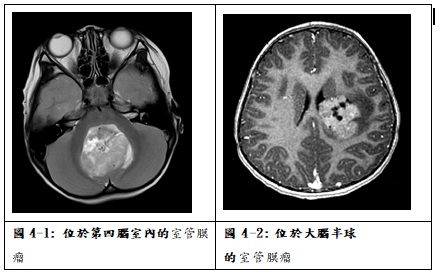

國內統計室管膜瘤約佔兒童腦瘤的5.6%,平均年齡10.7歲。病理診斷分為室管膜下瘤(Subependymoma, WHO grade I )、黏液乳頭狀室管膜瘤(Myxopapillary ependymoma, WHO grade I )、室管膜瘤(ependymoma, WHO grade II)及分化不良室管膜瘤(anaplastic ependymoma, WHO grade III )。室管膜瘤最常發生在後顱窩第四腦室內(圖4-1),常常造成阻塞性水腦症,病童表現症狀從緩慢的步態不穩到頭痛、嘔吐、視力模糊等。也可能發生在大腦半球(圖4-2),少數原發於脊椎內。